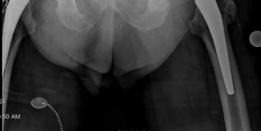

Previous surgical procedures : Right total hip arthroplasty 2008, left total hip arthroplasty 2011, inferior vena cava filter (Fig. 19.22).

Fig. 19.22 Most recent routine follow-up PA pelvis, prior to emergency department presentation. Evidence of significant femoral peritrochanteric and pelvic periacetabular osteolysis